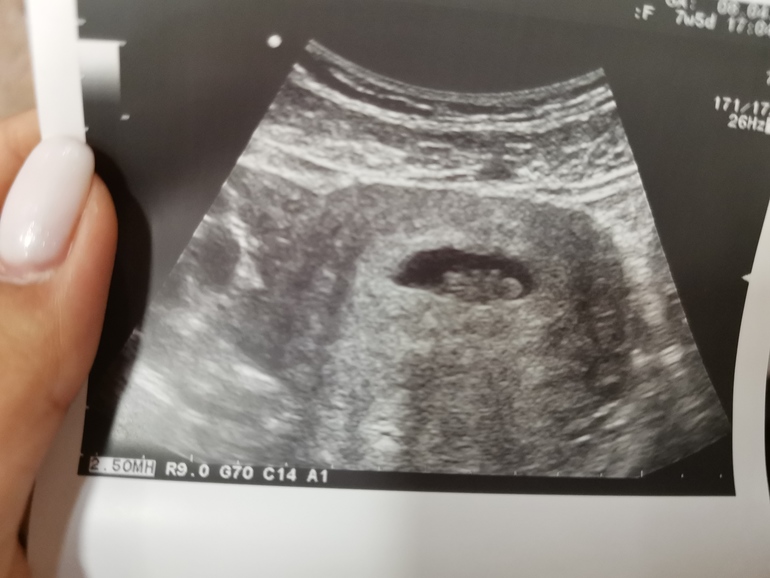

Первые фотки нашего ляля❤️

Решила оставить в дневнике и поделиться с вами, девочки, позитивными эмоциями🤗 Сделала для архива кассетный тест в 6 недель, а в 7+6 сходила на УЗИ увидеть малыша и послушать его сердечко. Он ещё совсем крошка, КТР 1.1см, но уже как-будто видно ручонки и головку👶 Расти, малыш, скоро ты будешь с нами❤️